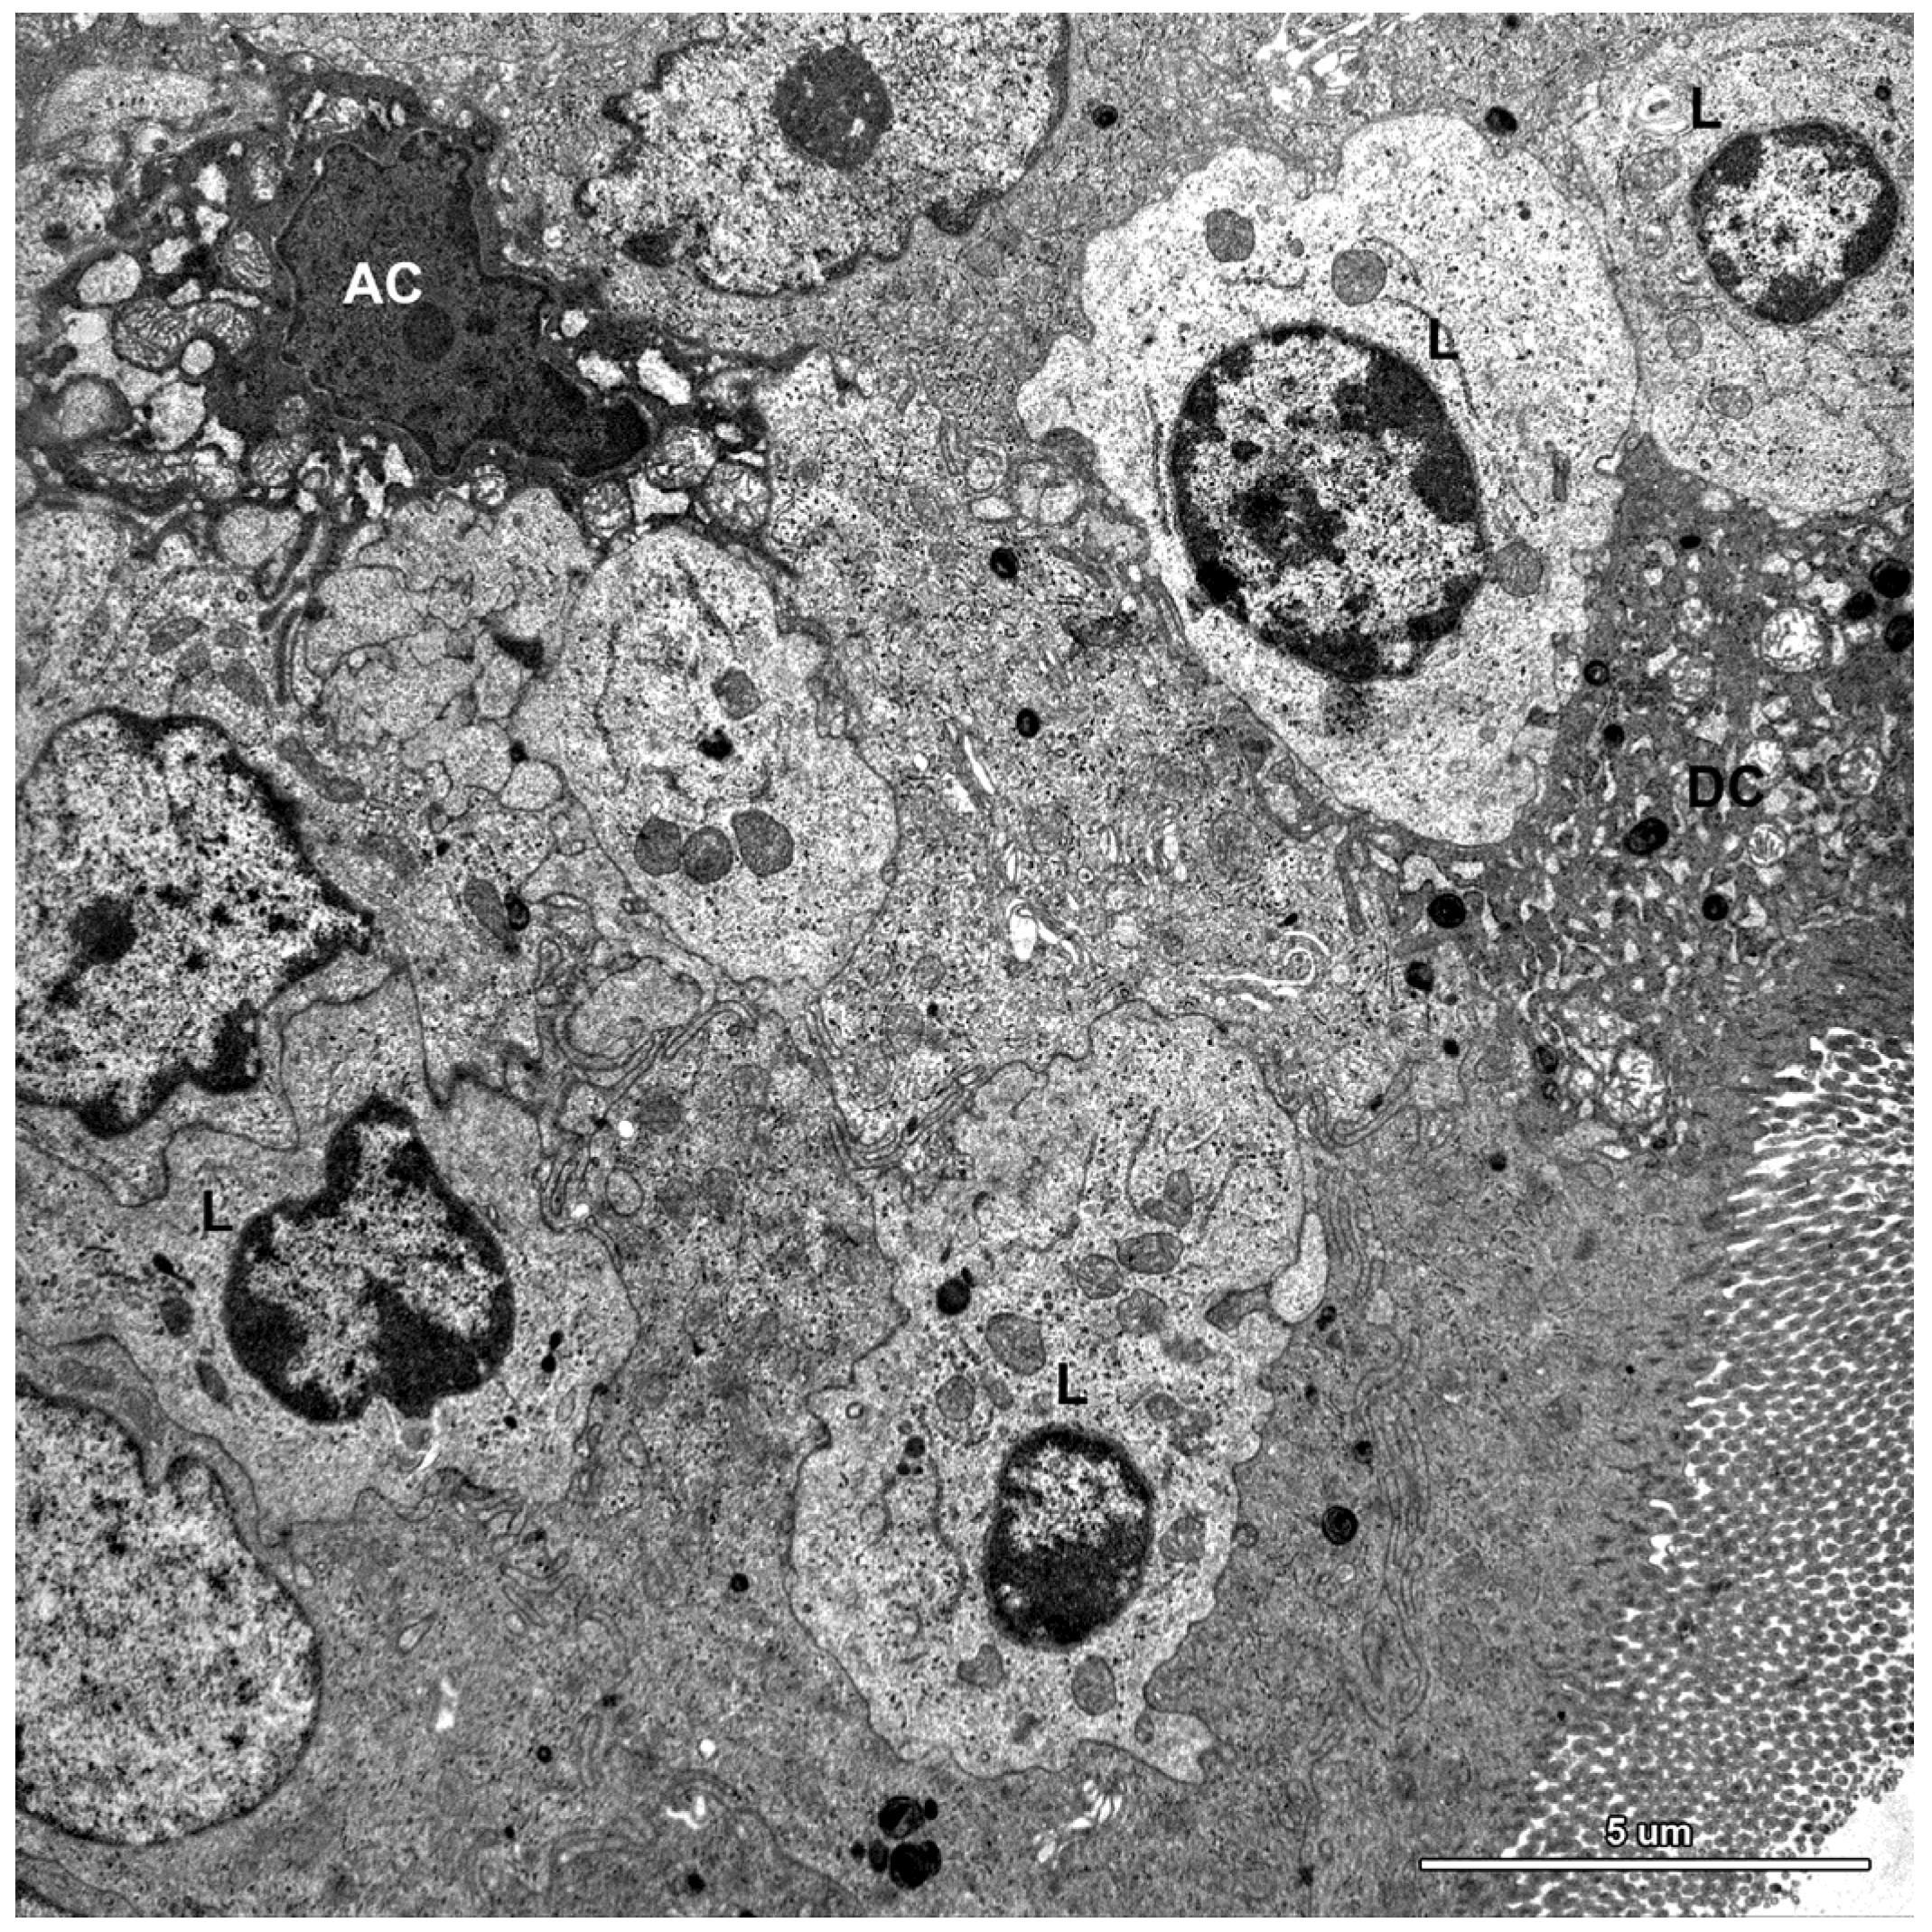

Figure 9.

Ultrastructure of the jejunal mucosa epithelium in a pig that received DON for six weeks. Note numerous lymphocytes (L) between epithelial cells, degenerating adsorptive enterocytes (DC), and apoptotic cells (AC).

A characteristic feature of the epithelium covering the villi was the presence of numerous lymphocytes in samples taken from pigs that received ZEN for one week as well as ZEN, DON or DON + ZEN for three and six weeks (Figure 7, Figure 8 and Figure 9).

Some degenerating cells and apoptotic cells were found in the epithelium in all animals (Figure 9); however, there were no difference in the frequency of their occurrence between groups.

The lamina propria of the jejunum of pigs treated with mycotoxins was formed by a loose connective tissue with numerous cells: fibrocytes and fibroblasts, lymphocytes, plasma cells, mast cells, eosinophils, and macrophages (Figure 10). Myocytes were observed inside of the villi (Figure 10). The difference between the groups was due to plasma cells, which were more numerous in the lamina propria of gilts treated with ZEN or DON for one, three, and six weeks than in the control pigs.